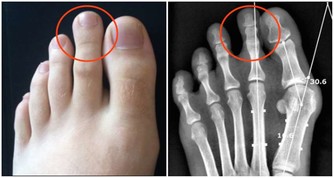

腳跟與人體的腎經關係密切,而顛腳跟實際上是刺激了腎經穴位。因為足少陰腎經起於足小趾下,斜行於足心湧泉穴,沿足跟部上行,最終屬腎絡膀胱。